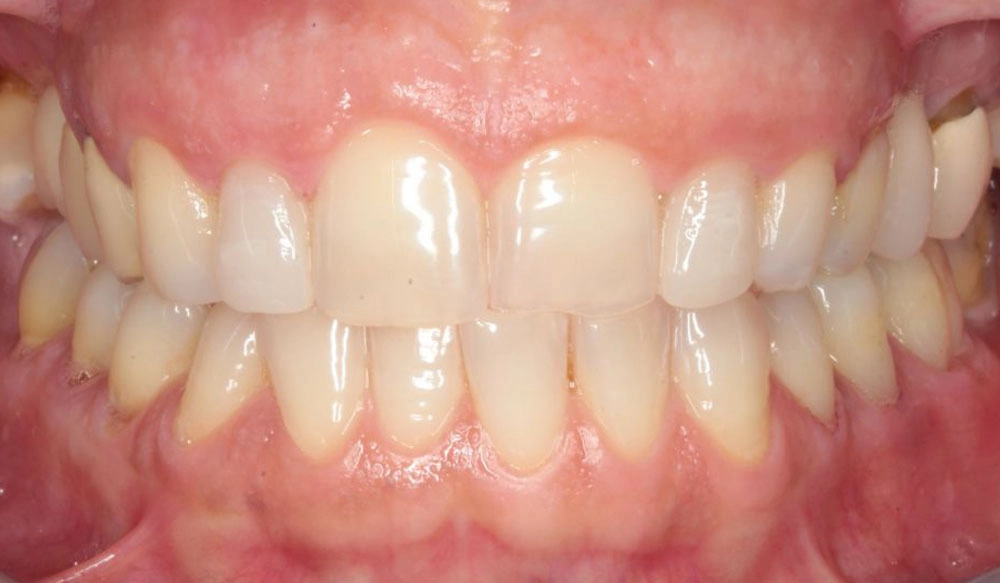

Deep Bite

Deep bite is the condition in which the vertical overlap of anterior teeth in centric occlusion is larger than 30 – 40%.

Patient Information:

Age: 13

Gender: Male

Invisalign Treatment Option: Invisalign Comprehensive

Total Treatment Time:

24 months